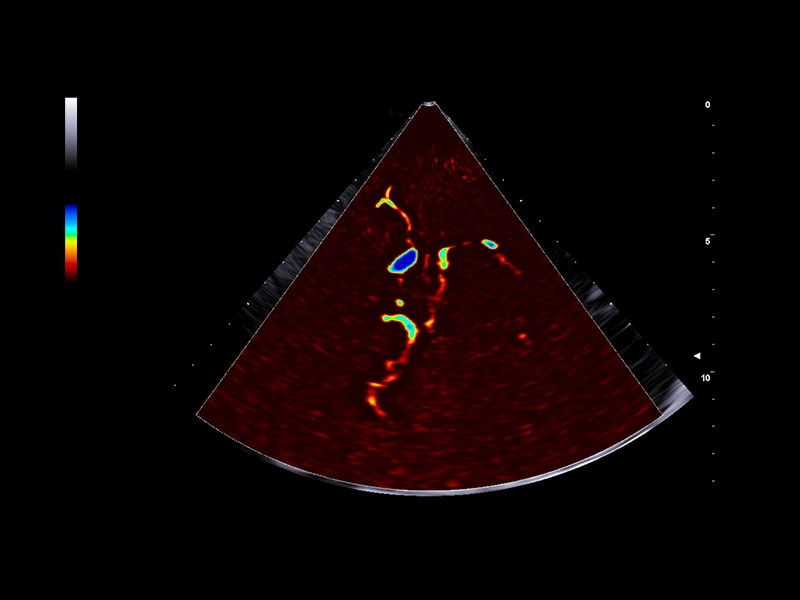

MyLab™9 Platform - Ultra-sensitivity Colour Doppler for precise visualization pulmonary veins

MyLab™9 Platform - Ultra-sensitivity Colour Doppler for precise visualization pulmonary veins